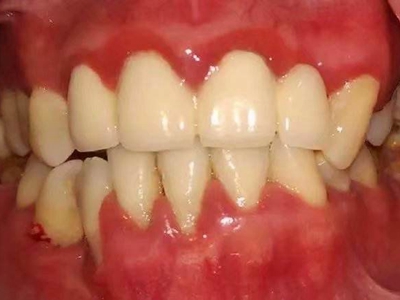

慢性龈炎又称边缘性龈炎或单纯性龈炎,主要表现为游离龈和龈乳头因炎性水肿,而变为鲜红或暗红色,龈缘变厚,龈乳头圆钝肥大。慢性龈炎的患病率高,治愈后仍可复发,部分患者可发展成为牙周炎。

慢性龈炎的病损部位一般局限于游离龈和龈乳头,以前牙区为主,尤其以下前牙区最为显著,患者常因刷牙或咬硬物时牙龈出血而就诊。游离龈和龈乳头颜色变为鲜红或暗红色,病变较重时炎性充血可波及附着龈。龈缘变厚,龈乳头圆钝肥大,可增生呈球状,覆盖牙面。牙龈松软脆弱,缺乏弹性。